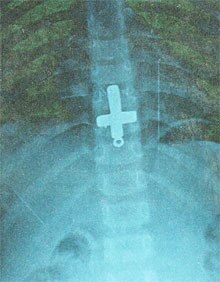

പെരിന്തല്മണ്ണ: അഞ്ച് വയസ്സുകാരിയുടെ വയറ്റില് കുടുങ്ങിയ കുരിശാകൃതിയിലുള്ള ലോക്കറ്റ് ശസ്ത്രക്രിയ കൂടാതെ പുറത്തെടുത്തു. വളാഞ്ചേരിക്കടുത്ത് ചെമ്പ്ര സ്വദേശിയായ സുരേഷ് ബാബുവിന്റെ മകളുടെ വയറ്റില് കുടുങ്ങിയ ലോക്കറ്റാണ് പെരിന്തല്മണ്ണ ഇ.എം.എസ് സഹകരണ ആസ്പത്രിയിലെ ഗ്യാസ്ട്രോ എന്റോളജി വിഭാഗം മേധാവി ഡോ.നന്ദകുമാറിന്റെ നേതൃത്വത്തിലുള്ള സംഘം പുറത്തെടുത്തത്.

കുട്ടിയെ ഉടനെ ഇ.എം.എസ് സഹകരണ ആസ്പത്രിയിലെത്തിച്ചു. ഡോ.നന്ദകുമാറിനെ കൂടാതെ ഡോ. കൃപാലി, ഡോ.ലീന, ടെക്നീഷ്യന് അഭിലാഷ്, പ്രസന്ന എന്നിവരുടെ നേതൃത്വത്തില് വളരെ ശ്രമകരമായ പ്രയത്നത്തിലൂടെയാണ് ശസ്ത്രക്രിയകൂടാതെ ലോക്കറ്റ് പുറത്തെടുക്കാനായത്. മൂന്ന് സെന്റിമീറ്റര് നീളവും നാല് സെന്റിമീറ്റര് വീതിയുമുള്ളതാണ് കുരിശാകൃതിയിലുള്ള ലോക്കറ്റ്.